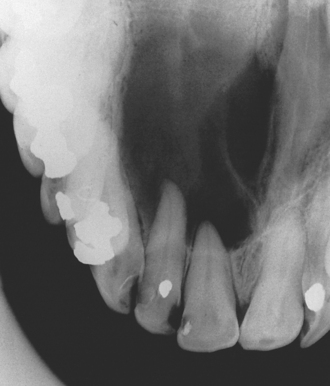

Intrabony cysts may remain symptomless for many years and only come to light as an incidental finding on routine dental inspection or radiographic investigation (Fig. 9.1) or can present in a variety of ways described below.

Fig. 9.1 Occlusal radiograph of a radicular (dental) cyst, displaying a well-defined radiolucency arising from a non-vital upper lateral incisor.